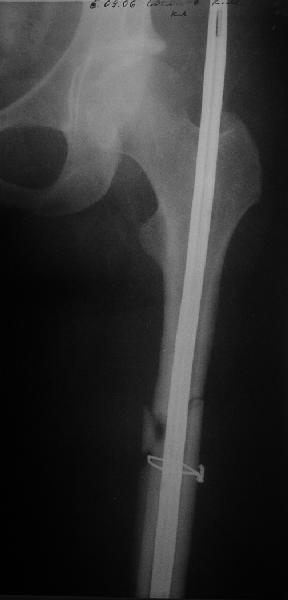

Уважаемые коллеги! Помогите определиться с дальнейшей тактикой лечения несращения бедра.

Пациент попал под наше наблюдение через 3 недели после первого

остеосинтеза (фото 1). Учитывая, нестабильность остеосинтеза,

выстоящий стержень закрыто перештифтовали (фото 2), через 3 месяца

динамизация. К 5 месяцам имели укорочение 2 см, при том, что

динамический винт стал статическим. От дальнейшей динамизации

отказались, учитывая наличие контакта между фрагментами и возможность

прогрессирования укорочения. К 1,5 года сращение не достигнуто (фото

3). Удалили гвоздь, выполнили дистракционный остеосинтез с целью

стимуляции остеогенеза и компенсации укорочения (фото 4), потом

закрыто перештифтовали после рассверливания (фото 5). На сегодняшний

день, через 4 месяца после последней операции (фото 6) признаков

регенерата нет, длина восстановлена, ходит без дополнительной опоры.

Возможные варианты: 1)подождать - однако регенерата не заметно

2)Снова потерять длину (динамизация, компрессирющий остеосинтез на

этом гвозде, после перепроведения проксимальных винтов и

копрессирующей заглушки, восстановление длины после сращения)

3)Костная пластика